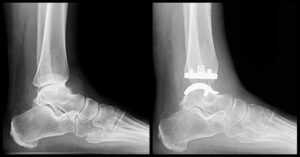

Prótesis de Tobillo